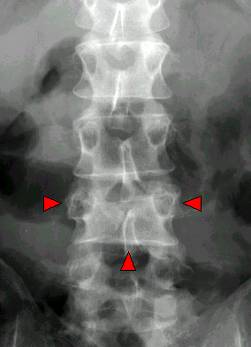

3.强直性脊柱炎 ( AS):以中轴关节慢性炎症为主的全身疾病,病因不明,类风湿因子阴性。病理学:非特异性炎症。;双侧骶髂关节受累;

脊柱韧带骨化—骨性强直—竹节状脊柱

病理改变:渗出轻,增殖为主。;韧带和关节囊的附着部炎症,导致韧带骨赘形成、椎体方形变、椎骨终板破坏、跟腱炎等。;易软骨化生及骨化。

X线表现:1.骶髂关节鼠咬状骨质破坏,狭窄或骨性强直,双侧对称;2.竹节状脊柱,纤维环和韧带的骨化、椎体方形变